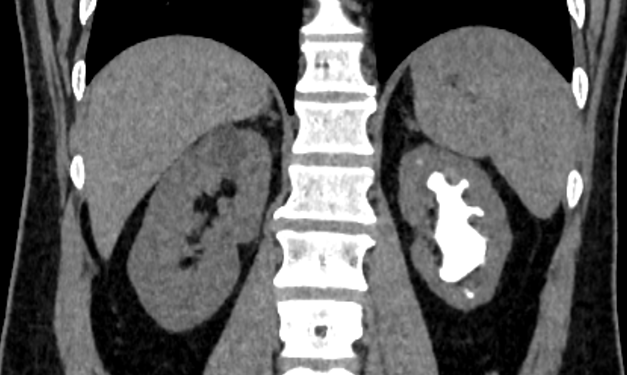

近日,我院泌尿外科浦金贤主任和周守军主任医师团队完成一例肾脏铸型结石经皮肾超声碎石手术,该名患者因“发现左肾结石2年,左侧腰痛3周”入院,诊断为左肾结石,其结石大小约6.8cm*3.8cm,为巨大完全鹿角形结石。结石不仅充满整个左侧肾盂、肾盏,更有部分向输尿管上段延伸。

术前,超声定位见结石充满肾盂、肾盏,肾脏几乎无积水,这对经皮肾穿刺通道的建立带来了很大的挑战,导丝极易滑脱或者穿透对侧肾实质,进而造成操作通道的丢失及肾脏大出血等严重并发症。

术中,周守军主任医师选择肾脏中盏背侧后组为穿刺路径,超声实时引导下,精准穿刺至目标肾盏,整个穿刺过程一气呵成,通过F20单通道配合第五代EMS(瑞士EMS超声弹道碎石系统)一次性完成超声碎石取石手术,术后复查无明显结石残留。通过此次手术,医生借由一个大小仅7mm的切口,就彻底清除了左侧肾内6.8cm大的结石,解除了困扰患者2年多的烦恼,患者对手术结果表示非常满意。